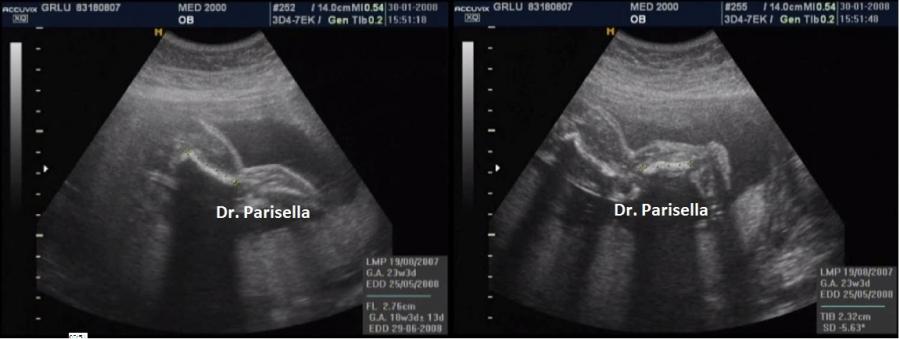

La Displasia Tanatofora tipo 1 è trasmessa con modalità autosomica dominante ed è caratterizzata principalmente da RIZOMELIA SEVERA, FEMORI CORTI (A CORNETTA DI TELEFONO), IPOPLASIA TORACICA SEVERA.

Dal punto di vista ecografico il tratto rizomelico è estremamente ipoplasico, ricurvo e con le metafisi slargate (Femore a Cornetta di Telefono) -  (il riconoscimento del Femore a Cornetta di Telefono rappresenta un segno importantissimo e sufficiente per porre con certezza la diagnosi di Displasia Tanatofora tipo I); vi sono coste corte con ipoplasia toracica e si osserva il classico gradino al passaggio tra torace ipoplasico e addome apparentemente prevalente; vi è in genere macrocrania con bozze frontali prominenti (frontal bossing) e naso a sella. Si associa polidramnios severo.